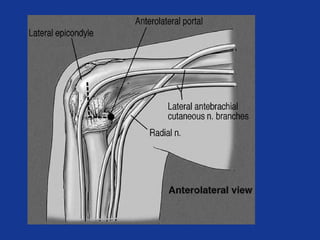

Arthroscopy

• 70% satisfactory to excellent

• 473 cases

– 4 deep infection

– 33 prolonged drainage

– 12 transient nerve palsies

Arthroscopic tennis elbow release. Kalainov D et al. Techniques in Hand and Upper Extremity

Surgery. 2007;11(1):2-7

• Arthroscopy leaves residual tendinopathy

– Gross and histological

– Results in poorer outcomes

Lateral Epicondylitis: In Vivo Assessment of Arthroscopic Debridement and Correlation With

Patient Outcomes. Cummins CA. Am J Sports Med Sep 2006, 34(9):1486